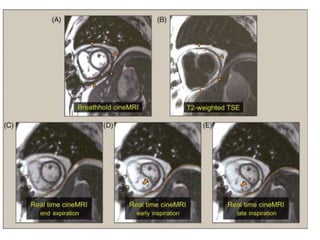

• Constrictive Pericarditis

• Realtime CineMRI

• increased ventricular interdependence, a

hemodynamic hallmark of pericardial constriction.

Pericardial Disease • ConstrictivePericarditis • > 4 mm abnormal • <2 mm normal • TSE morphology and SSFP • Realtime CineMRI • increased ventricular interdependence, a hemodynamic hallmark of pericardial constriction.

• #86 Breath-hold cineangiocardiographic (cine) MRI (single phase shown) and T2-weighted turbo spin echo imaging shows marked pericardial thickening (orange arrowheads). Real-time cineMRI demonstrates displacement of the interventricular septum (orange arrows) toward the left ventricle during early inspiration, consistent with ventricular interdependence. The dotted orange line highlights the movement of the diaphragm.